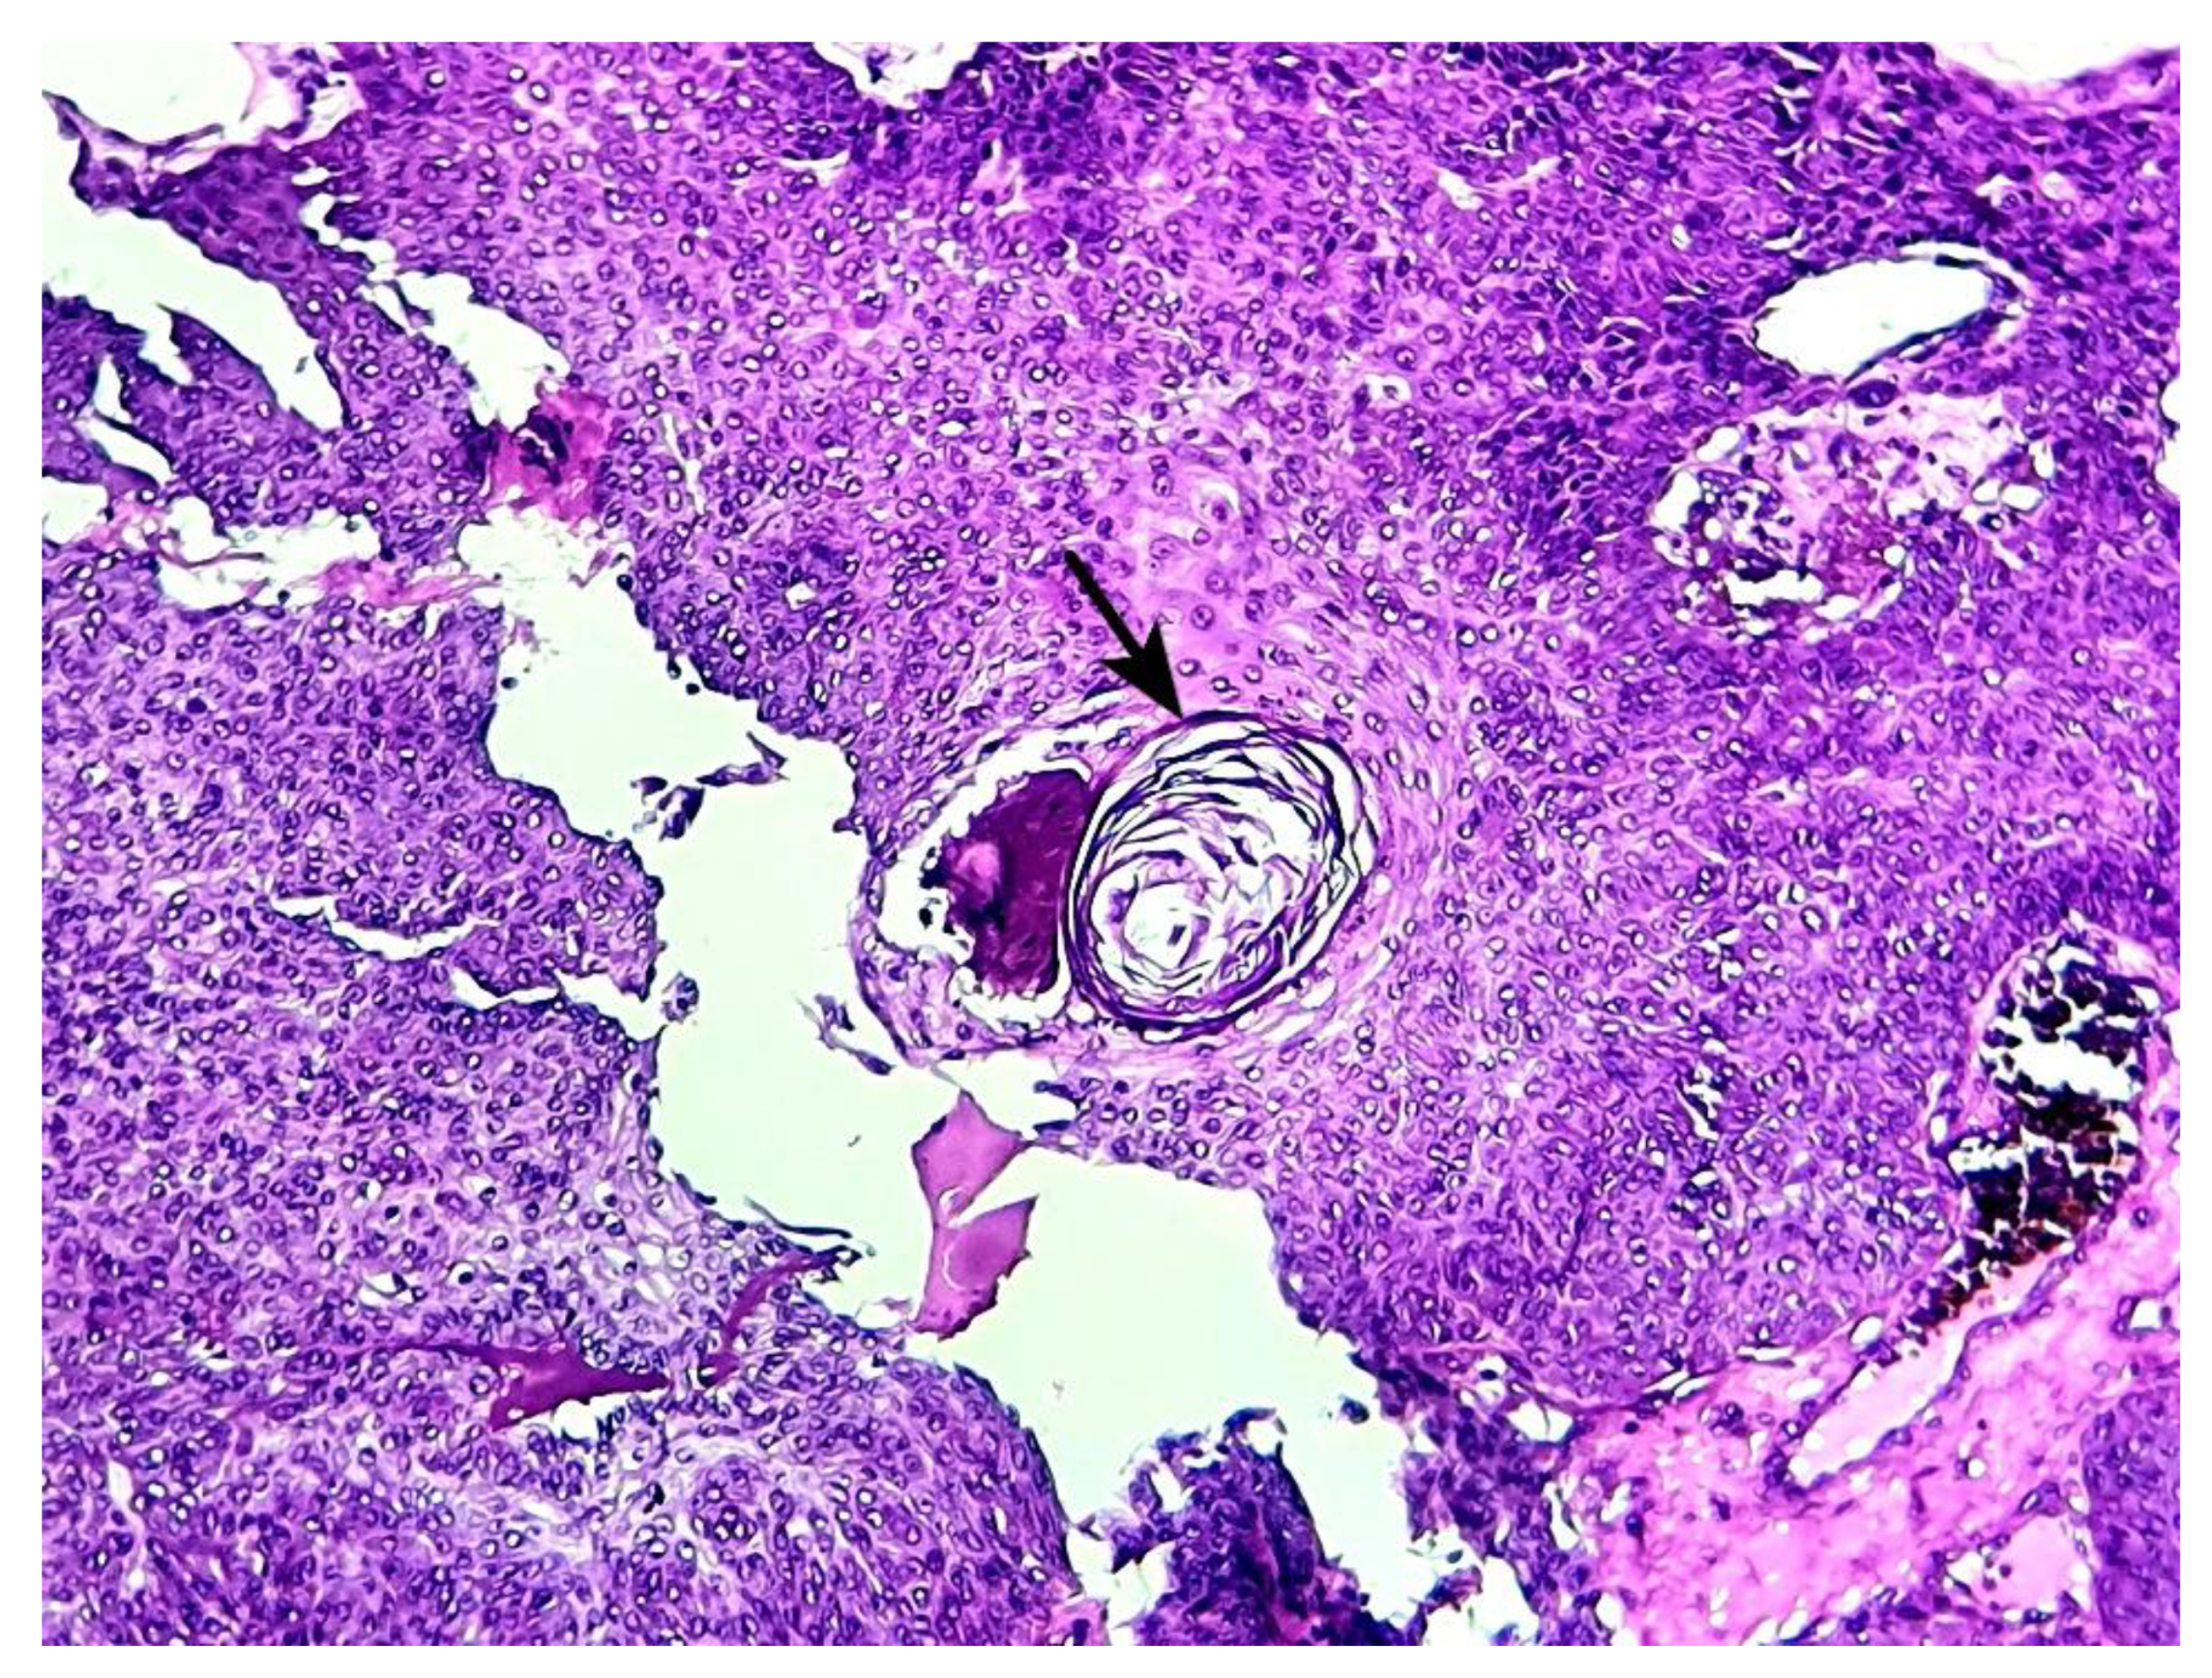

Ductal structures were generally dilated and cystic with eosinophilic amorphous contents, with pure eccrine differentiation in 7/13 cases (53.8%) (Figure 4 a, arrow), mixed eccrine/apocrine differentiation in 5/13 patients (38.5%) and 1 pure apocrine differentiation (bulging apical cytoplasm with decapitation secretions) (Figure 4 b, arrow).

Focal keratin horns were present in 2 patients (15.4%) (Figure 5, arrow), while focal poroid cells maturation as squamous eddies were found in 6 cases (46.2%) (Figure 6, arrow).

Figure 4. a: Eccrine ductal differentiation shown as a small duct lined by flat cells with conspicuous eosinophilic cytoplasm (black arrow) (hematoxylin-eosin x 200) (case 5). b: Apocrine ductal differentiation seen as a cystic duct lined by epithelial cells with bulging apical eosinophilic cytoplasm with decapitation secretion (black arrow) (hematoxylin-eosin x 400) (case 9).

Figure 5. Horn cyst consisting of focal concentric lamellar keratin within a microcystic space (hematoxylin-eosin x 200) (case 1).